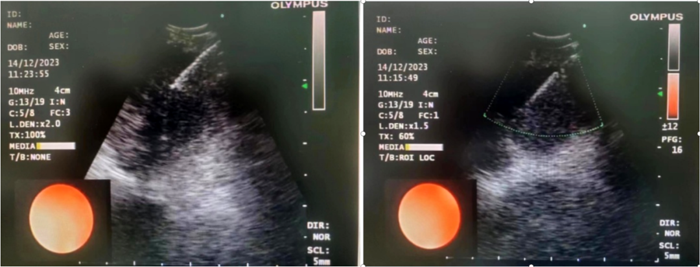

患者,女,72歲,2月來(lái)“反復(fù)咳嗽、咳痰,偶咳白痰中帶血絲”,胸部CT提示“肺占位、肺炎”,收住院。完善胸部強(qiáng)化CT提示“左肺占位、肺炎、縱膈多發(fā)淋巴結(jié)腫大”,電子支氣管鏡檢查見(jiàn)左肺上葉支氣管血塊及壞死物阻塞,清除后見(jiàn)管腔通暢,刷檢DNA細(xì)胞學(xué)示“細(xì)胞退變明顯,建議進(jìn)一步檢查”。10月27日行CT引導(dǎo)下肺穿刺活檢,病理示“機(jī)化性肺炎”,給予抗感染及激素治療,患者癥狀好轉(zhuǎn)出院。半月前,患者復(fù)查肺CT發(fā)現(xiàn)病灶較前稍有增大,張強(qiáng)主任考慮患者癥狀雖有好轉(zhuǎn),但仍存在腫瘤性病變可能性。經(jīng)過(guò)討論及與患者家屬充分溝通后,決定實(shí)施支氣管內(nèi)超聲引導(dǎo)下針吸活檢術(shù)(EBUS-TBNA)+電子支氣管鏡檢查+現(xiàn)場(chǎng)快速評(píng)價(jià)(ROSE)技術(shù),以提高診斷陽(yáng)性率。術(shù)中ROSE提示查找到可疑癌細(xì)胞,取材量較足分。最后病理檢查明確診斷為低分化肺腺癌,隨后進(jìn)行基因檢測(cè),明確了治療方向。

患者,男,70歲,近2個(gè)月來(lái)“活動(dòng)后呼吸困難,近日又出現(xiàn)痰中帶鮮血”,收住院。胸部增強(qiáng)CT見(jiàn)“左肺下葉外周型占位,肺門(mén)、縱膈淋巴結(jié)腫大”。張強(qiáng)主任帶領(lǐng)團(tuán)隊(duì)討論分析患者病情,高度懷疑為腫瘤性病變,且普通電子支氣管鏡獲取組織困難,病變緊貼主動(dòng)脈,經(jīng)皮肺穿刺活檢風(fēng)險(xiǎn)大。為明確診斷及分期,決定為患者實(shí)施支氣管內(nèi)超聲引導(dǎo)下針吸活檢術(shù)(EBUS-TBNA)+電子支氣管鏡下病灶活檢+現(xiàn)場(chǎng)快速評(píng)價(jià)(ROSE)。術(shù)中ROSE快速診斷查找到肺腺癌細(xì)胞,手術(shù)過(guò)程順利。最后病理檢查明確診斷為肺腺癌,為患者的下一步治療確定了方向。